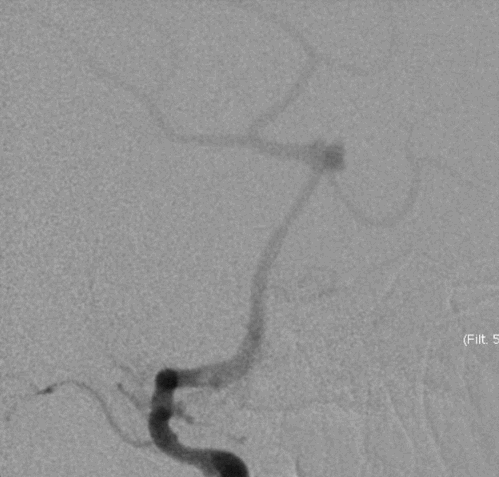

Tubridge Plus Case 3